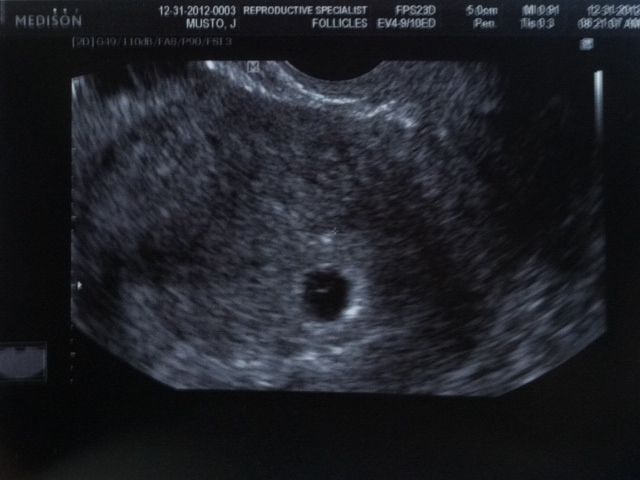

First Sono Went well!!!

I had my first sono on Monday. We have 1 sac with a Yolk!!!! They thought there was another sac present but it looks like it's just flulid. That sono is in pic #2. While it's still very early I am very nervous!! We go in on Monday, 1/7/12 for the second Sono and we get to hear the baby's heartbeat for the first time!! I was thinking of having DH recording it..If it's allowed!!

YEAH!! That's a great looking sac you got right there